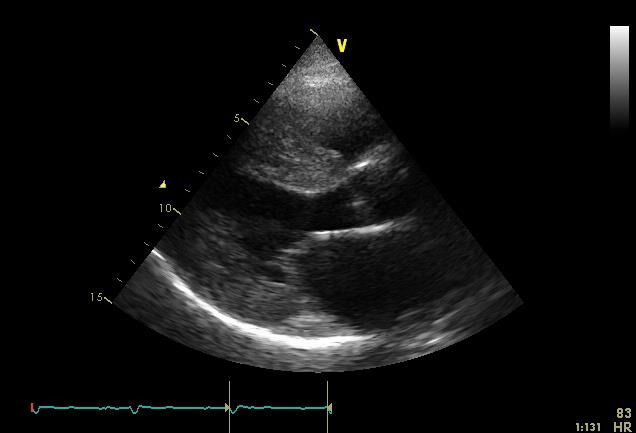

これらの所見は心アミロイドーシスの特徴である。アミロイドーシスとは、異常蛋白(アミロイド)が全身の臓器、特に心臓、肺、肝臓、胃、腸、腎臓などの臓器に沈着して、いろいろな臓器の機能が低下して発病する疾患である。心アミロイドーシスでは、アミロイドが心室筋の間に沈着し、心室の拡張障害、さらには収縮機能の障害をきたし、最後には重症の心不全と不整脈により死亡する疾患である。心エコー検査では、心室壁全体が肥厚しており、収縮機能は保たれているものの、高度の拡張障害を認めた(図3)。心臓カテーテル検査では、冠動脈に異常なく、右室心筋生検にて心筋自体に空砲変性と軽度の肥厚を認め、間質にアミロイド蛋白の沈着を認めた。

図3-心エコー図